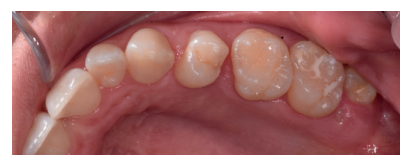

Se presenta un caso clínico de una mujer de 20 años de edad, que acudió remitida por su ortodoncista para la extracción de un premolar retenido maxilar, en posición invertida, previo a la realización de tratamiento ortodóntico. Se realizó la Historia Clínica de la paciente, que no presentó antecedentes médico-quirúrgicos de interés, alergias medicamentosas conocidas ni hábitos nocivos. A la exploración extraoral no se apreció ningún dato relevante. A la exploración intraoral, la paciente presentó la ausencia en boca del segundo premolar superior izquierdo y la presencia de los terceros molares inferiores retenidos (Figuras 1, 2 y 3).

A la exploración radiográfica mediante radiografía panorámica se apreciaron ambos terceros molares inferiores retenidos, en una posición mesioangular, los superiores retenidos en posición vertical y la presencia de un premolar maxilar retenido, en posición invertida, en el segundo cuadrante (Figura 4).